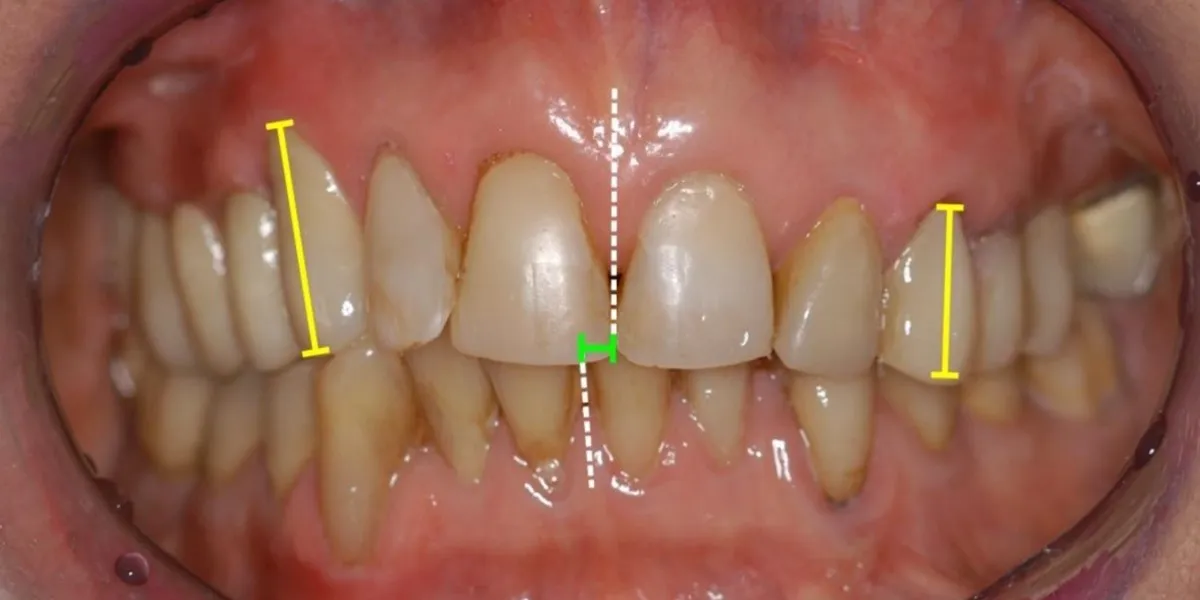

- ایجاد فضای خالی یا جابهجایی دندانهای مجاور

- تغییر شکل یا کجی دندانهای جلو

درمان صحیح دندان نیش نهفته نه تنها عملکرد جویدن را بهبود میدهد بلکه به زیبایی لبخند نیز کمک میکند. ارتودنسی مناسب از جابهجایی دندانهای مجاور جلوگیری کرده و از فشار اضافی به فک و لثه جلوگیری میکند.